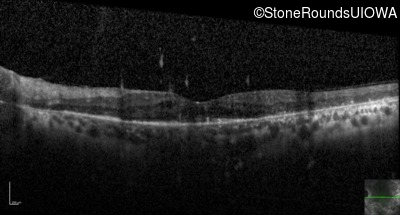

Optical Coherence Tomography - Right - 20/30

Exemplar / OCT Stack